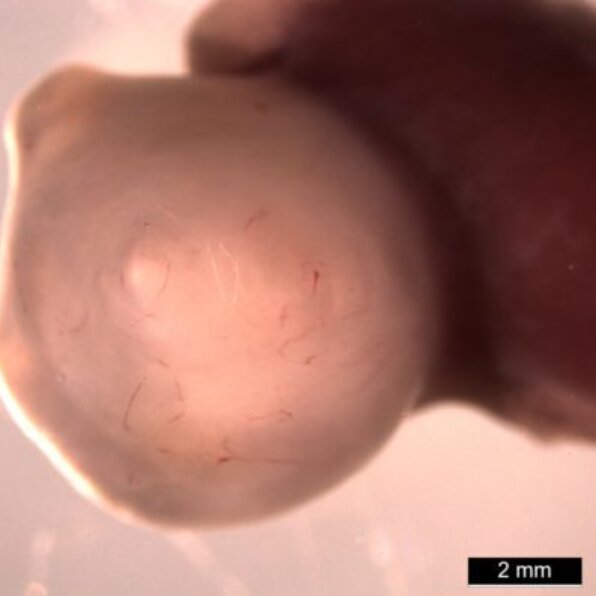

یک ارگانوئید ۱۰ هفتهای معده در بدن موش

محققان برای بهبود هرچه بیشتر این ارگانوئیدها پس از ۳۰ روز آنها را به موشها پیوند زدند. ارگانوئیدها در بدن موش با جریان خون تغذیه میشوند و فضای بیشتری دارند بنابراین هزاران برابر بزرگتر از حالت آزمایشگاهی رشد میکنند. این ارگانوئیدها ویژگیهای دیگری مثل غدد برونر(Brunner) ایجاد کردند. این غدد محلولی قلیایی ترشح میکنند که از بخش فوقانی روده در برابر اسید معده محافظت میکند.